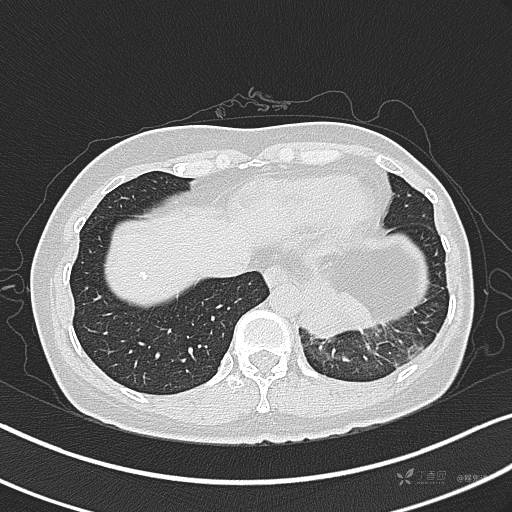

增强静脉期

静脉期CT值约84HU

CT值:平扫:31HU,动脉期:74HU,静脉期:84HU